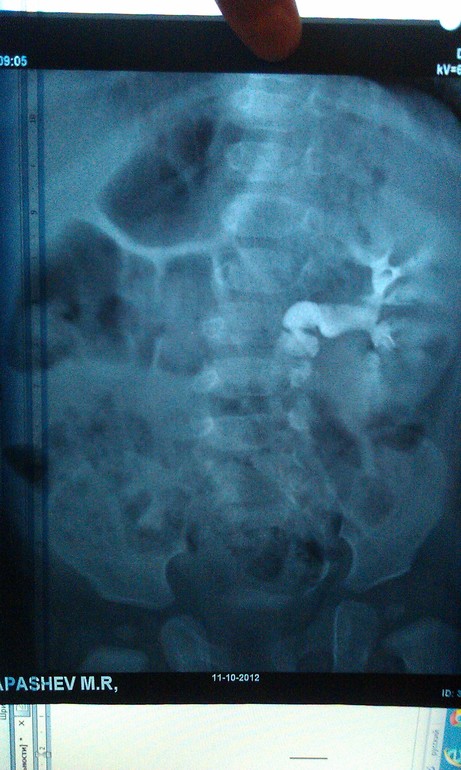

Олеся, не имея снимков в руках я не могу ручаться за какие то увиденные нюансы, разрешение не то. Справа есть тень, но тень это кишечника или тазовая дистопия почки я понять не могу. Слева гидронефроз это понятно, но вам только экскреторной урографии недостаточно для обследования. Надо делать цистографию, что бы исключить рефлюксирующий мегауретер, а для выяснения функции правой почки надо делать нефросцинтиграфию. Но это мое субъективное мнение, без знания ситуации сложно говорить о чем то определенно